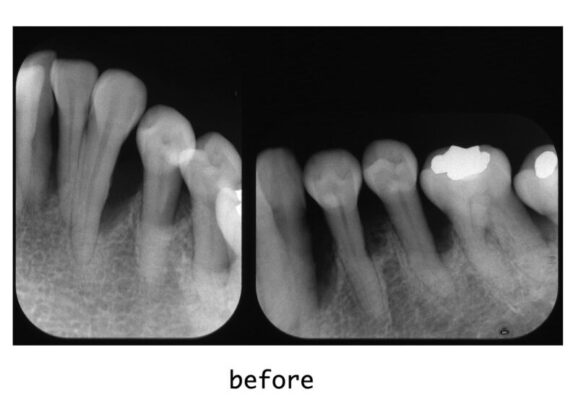

治療内容 お口全体の精密検査の結果、全体的に重度の歯周炎(歯周病)と診断されました。特に左下の奥歯周辺では、歯を支えるあごの骨が歯の根の長さの2/3以上失われている「垂直的骨吸収」が認められました。

まずは基本治療として5ヶ月間、ブラッシング指導(OHI)を行い、歯石除去(スケーリング)、および歯周ポケット奥深くの汚れを取り除く処置(SRP)を行って、お口の中の炎症を鎮めました。 その後、再評価検査を経て、骨が大きく失われている部位に対して「歯周組織再生療法」を行いました。エムドゲイン(歯周組織再生材料)と骨移植材料を併用し、失われた支持組織の再生を促しました。